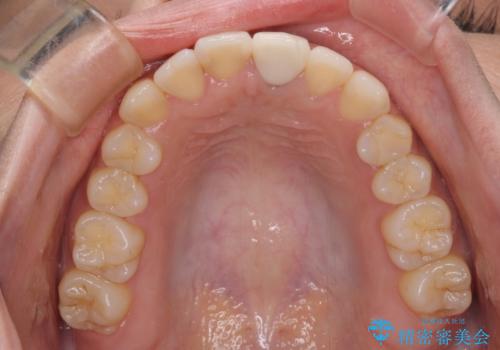

前歯のクロスバイトと変色した歯 ワイヤー矯正とセラミック治療

- 前歯のクロスバイトと神経を取り除いた後に変色してしまった前歯を気にして来院された患者様です。

ワイヤー矯正により矯正治療を行った後に、前歯の補綴治療を行うこととしました。

変色してしまった前歯は、反対側の歯と比べて歯肉が覆い被さっていたため、骨整形を含めた歯周外科処置を行い、歯肉ラインを整えることとしました。